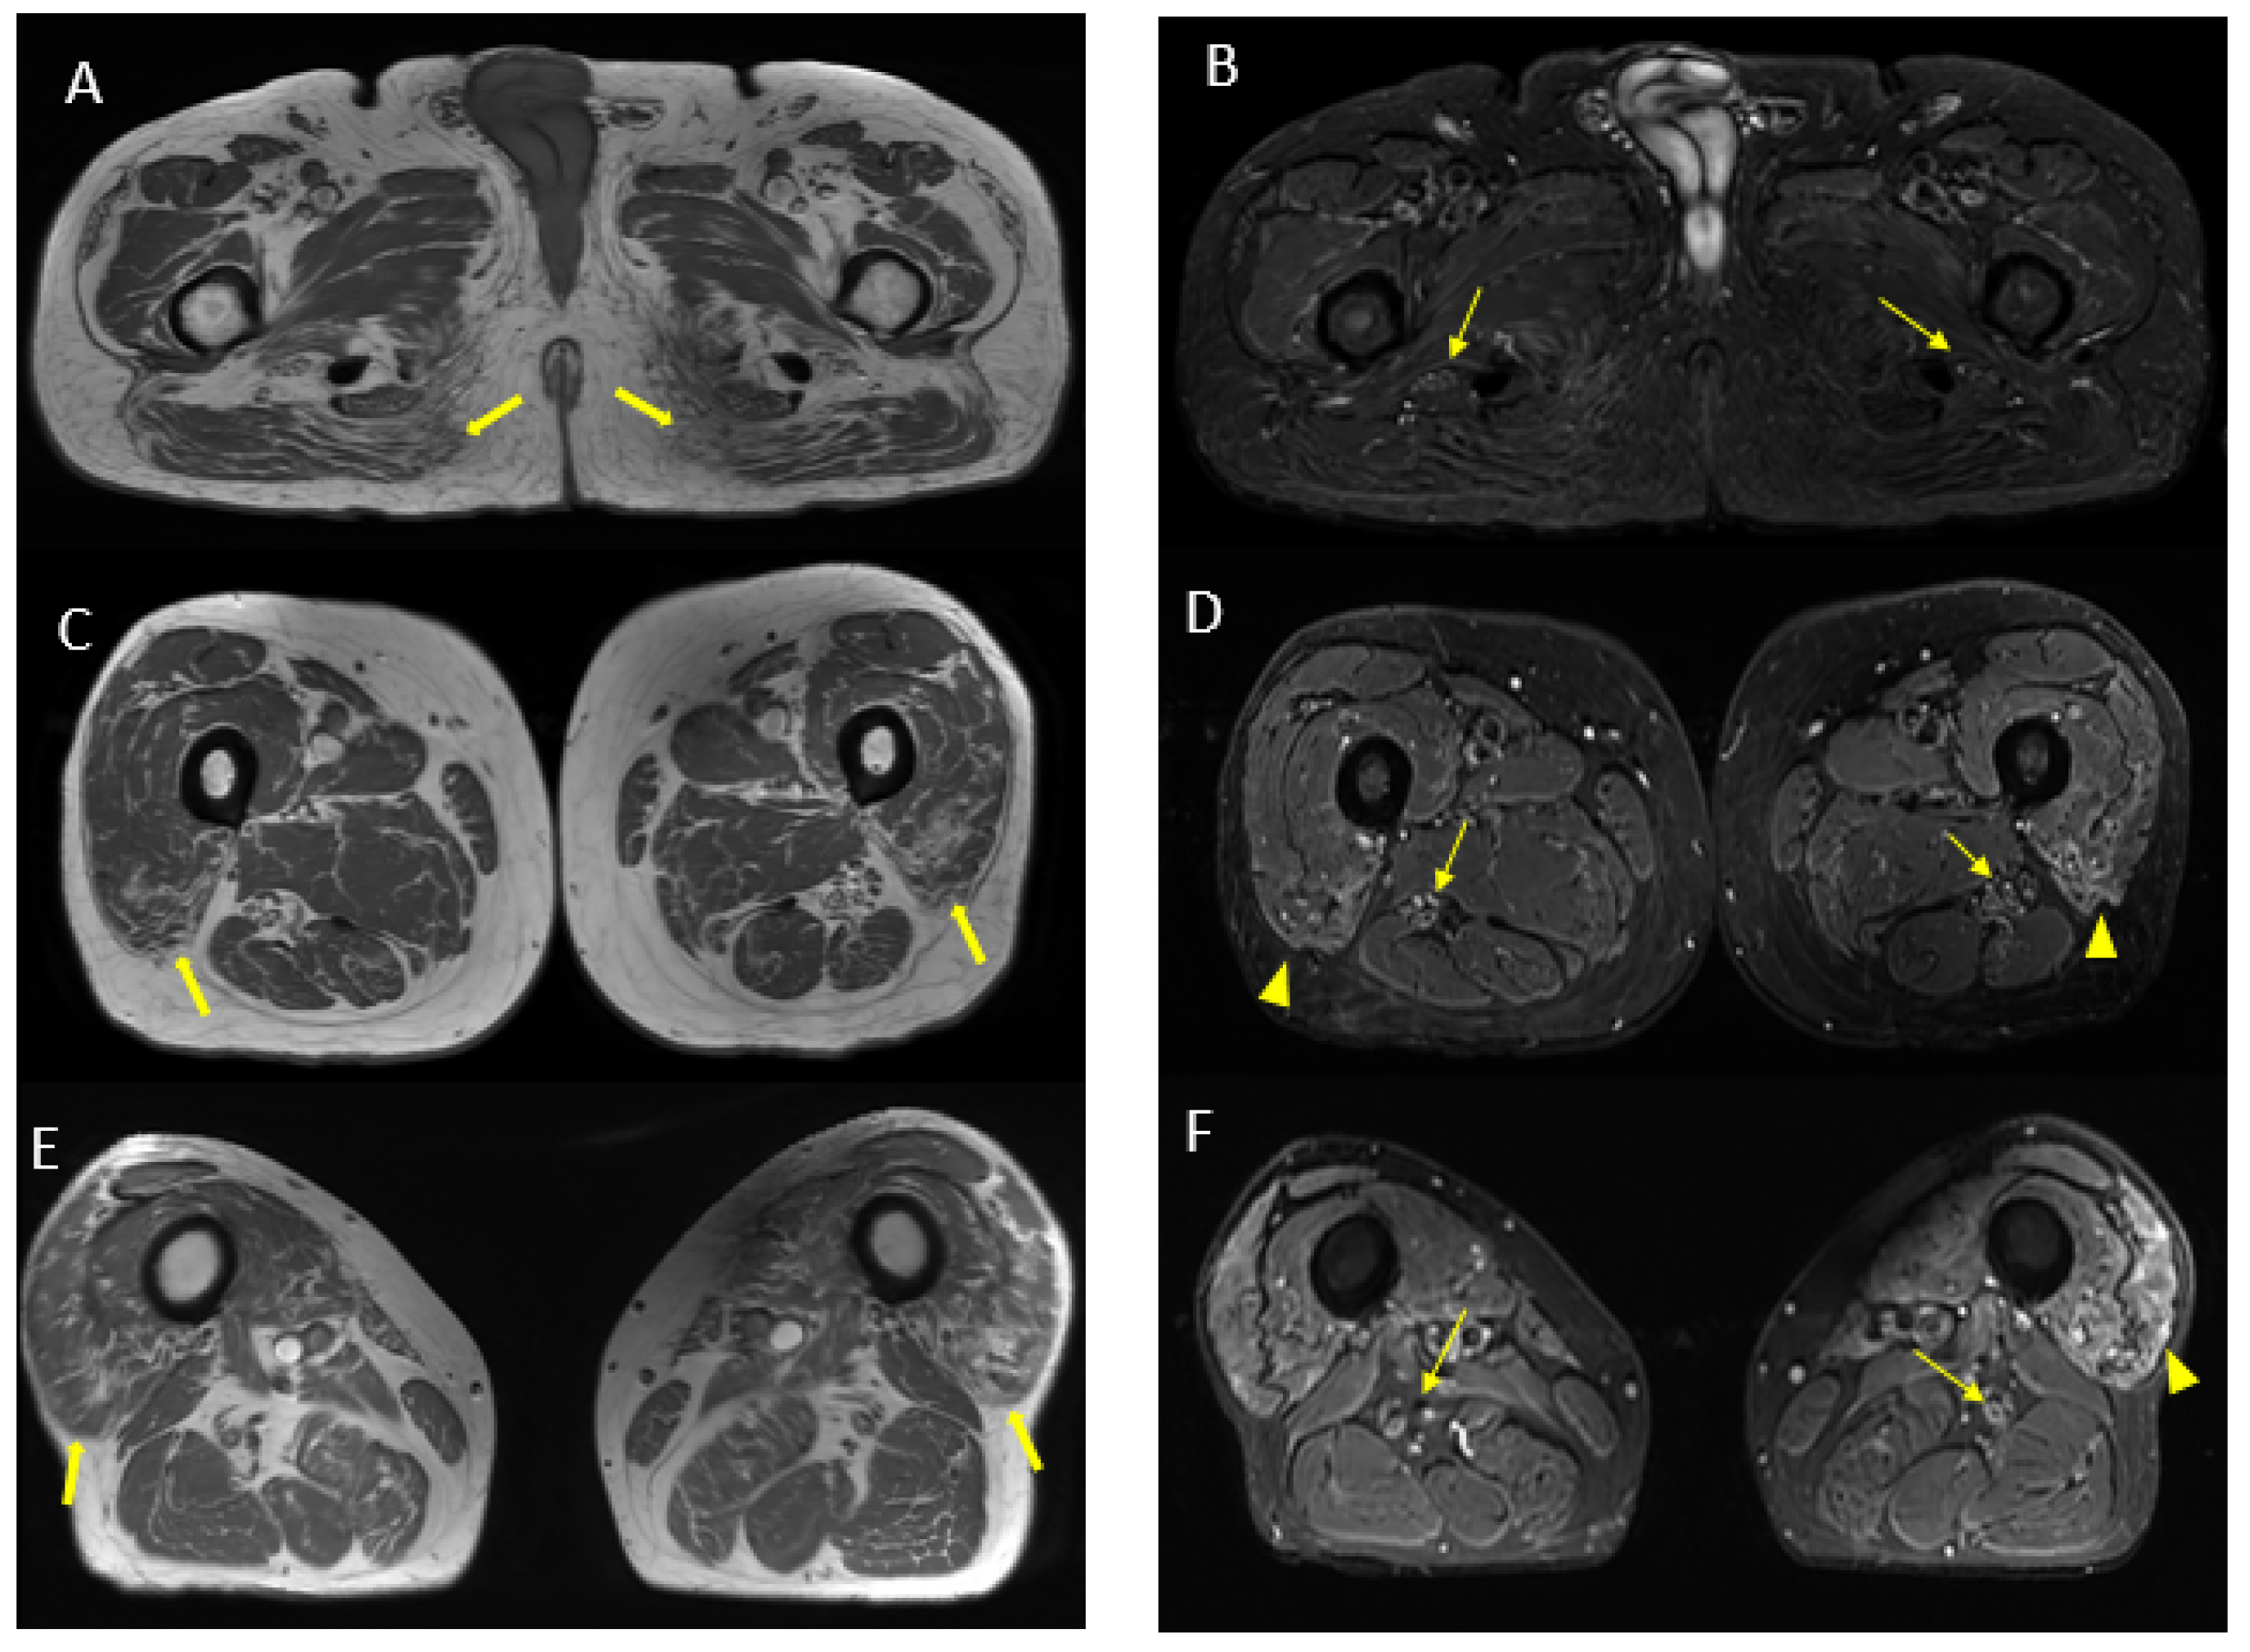

MR findings: brain and spinal MR were negative for pathological contrast enhancement of the roots of the cauda equina and radicles emerging from the spinal cord. Instead, swellings along the extracranial course of some V and VI cranial nerve branches had been reported (Figure 1). It was decided to integrate the study with MR neurography of the cranial nerves and the lumbosacral and brachial plexuses, which showed diffuse hypertrophy of the cranial nerves, and in particular of the oculomotor, trigeminal, facial, and hypoglossal (Figure 2) nerves with bilateral associations and asymmetric hypertrophy of the lumbosacral (Figure 3 and Figure 4) and brachialis (Figure 3 and Figure 5) plexuses.

Figure 2.

MR (multiplanar reconstructions) of 3D cube neurography images show pathological, thickened cranial nerves along their extracranial course, with some cystic-like components. The images show the involvement of trigeminal branches V1 in ((D)—yellow star), V2 in ((B,D)—curved arrows with a transverse diameter after inferior orbital foramen: left 1.8 mm; right 2.6 mm) and V3 from its passage in the foramen ovale (asterisks in (A,B)) to its lingual (arrowheads in (B,D)) and alveolar divisions (thick arrows in (B–D)); the involvement of the left facial nerve in its intraparotid course (thin arrows in (A,C)) and the hypoglossal nerve (open arrow in (B), transverse diameter at C1 level: left 4.6 mm; right 2.1 mm).

MR findings: regular size and signal intensity of lumbar and sacral roots (Figure 6). Bilateral and symmetrical sciatic nerve T2 enlargement and fascicular hyperintensity (Figure 7). Mixed acute and chronic denervation of the muscles of the anterolateral compartment of the thigh. Mainly chronic denervation of the gluteal muscles (Figure 7).

Figure 7.

Axial 2D MR of sciatic nerve; on the left are the T1w images and on the right are the T2 STIR images. Bilateral and symmetrical sciatic nerve T2 enlargement and fascicular hyperintensity at the level of the gluteal region (thin arrows (B); CSA of sciatic nerve of 103 mm2 on the right; 90.1 mm2 on the left) and at the mid-thigh (thin arrows in (D,F)). Mixed, acute and chronic denervation of the muscles of the anterolateral compartment of the thigh with denervation edema (hyperintensity in STIR, arrowheads in (D,F)) and fat replacement (thick arrows in (C,E)). Mainly chronic denervation of the gluteal muscles (hyperintensity in T1w, thick arrows in (A)).